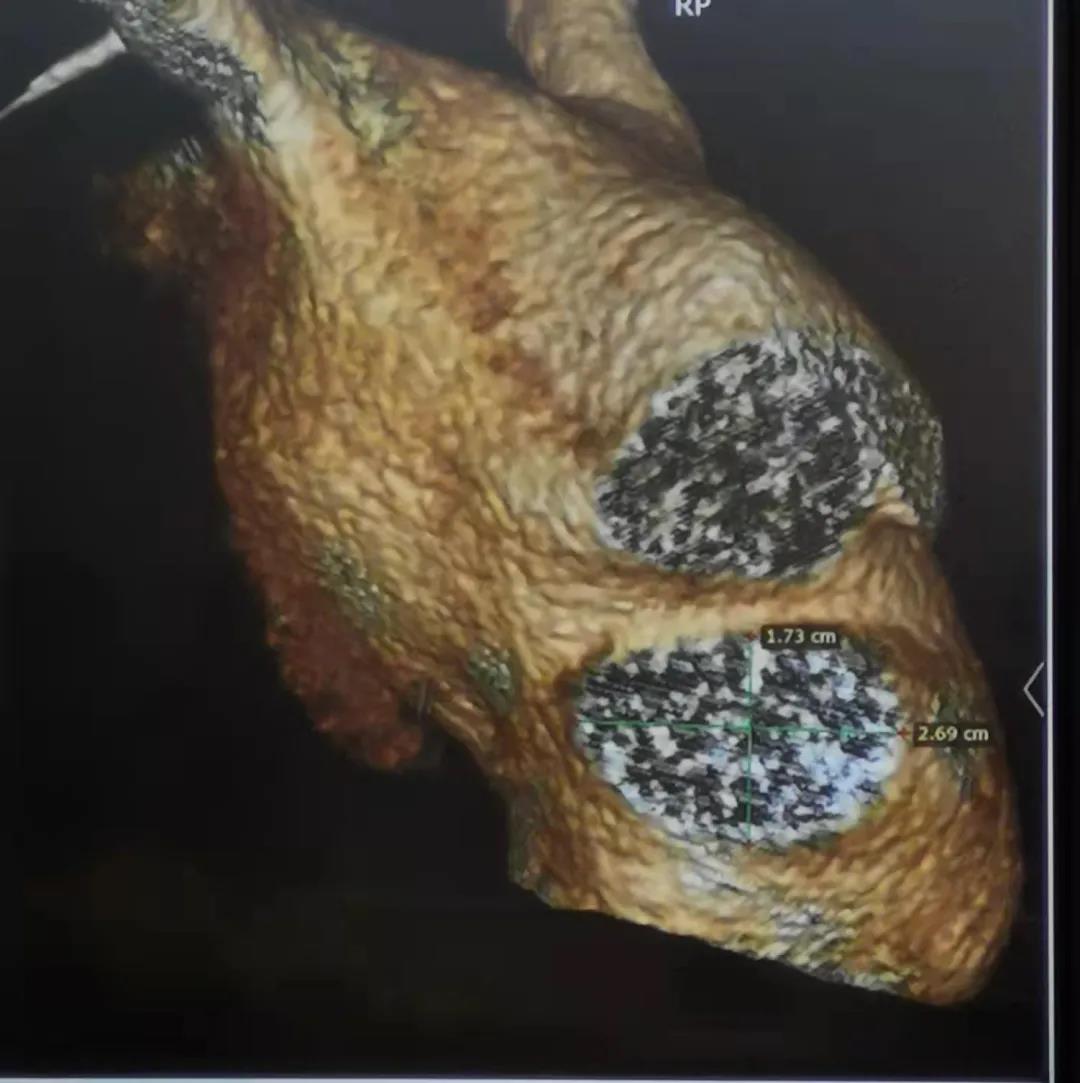

患者为66岁男性,患有持续性房颤、冠状动脉粥样硬化、高脂血症。术前CT三维重建显示左心耳开口为17*27mm,选用LAmbre™2228封堵器进行封堵,多角度造影及TEE显示封堵效果理想,无残余分流。LAmbre™更为纤细的输送鞘可以有效减少医源性损伤的发生,患者术后恢复良好。